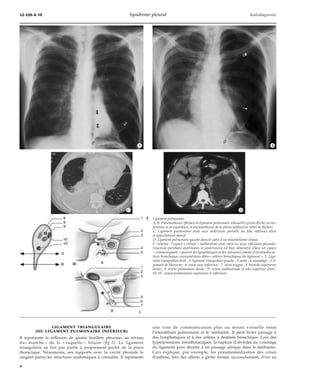

5 Ligament pulmonaire.

A, B. Pneumothorax (flèches) et ligament pulmonaire silhouetté (grosse flèche) en ins-piration

et en expiration, et pneumothorax de la plèvre médiastine (têtes de flèches).

C. Ligament pulmonaire droit avec atélectasie partielle du lobe inférieur droit

et épanchement massif.

D. Ligament pulmonaire gauche dans le cadre d’un mésothéliome évolué.

E. Schéma : l’espace « virtuel » médiastinal situé entre les deux réflexions pleurales

(viscérale-pariétale) antérieures et postérieures est bien démontré. Dans cet espace

« communiquant » passent des lymphatiques et des vaisseaux comme d’éventuelles ar-tères

bronchiques surnuméraires dites « artères bronchiques du ligament ». 1. Liga-ment

triangulaire droit ; 2. ligament triangulaire gauche ; 3. aorte ; 4. oesophage ; 5. li-gament

de Morozow ; 6. veine cave inférieure ; 7. veine azygos ; 8. bronche supérieure

droite ; 9. artère pulmonaire droite ; 9’. artère médiastinale et lobe supérieur droit ;

10-10’. veines pulmonaires supérieure et inférieure.

une voie de communication plus ou moins virtuelle entre

l’interstitium pulmonaire et le médiastin. Il peut livrer passage à

des lymphatiques et à des artères à destinée bronchique. Lors des

hyperpressions intrathoraciques, la rupture d’alvéoles au voisinage

du ligament peut aboutir à un passage aérique dans le médiastin.

Ceci explique, par exemple, les pneumomédiastins des crises

d’asthme, lors des efforts à glotte fermée (accouchement, drive au